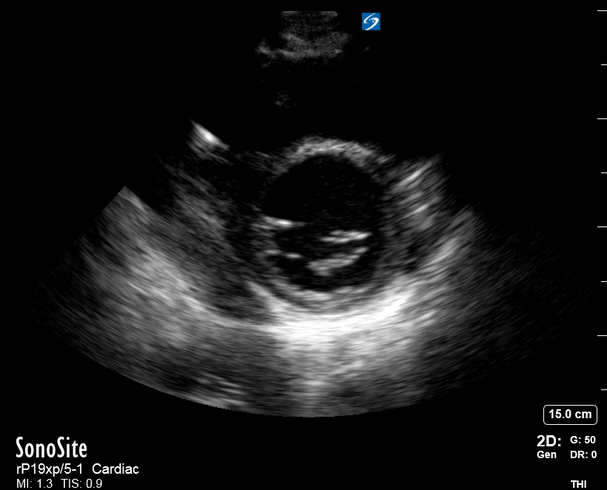

E-POINT SEPTAL SEPARATION

Active movement of the MV anterior leaflet during diastole, so it nearly touches the septum, correlates with good LV filling and ejection fraction. This can be assessed objectively by measuring the E-point septal separation (EPSS), which is the distance between the septum and the mitral anterior leaflet either in B-mode or M-mode. EPSS < 7mm is considered normal. EPSS is a good surrogate measure of ejection fraction, but it should be used with caution, as septal hypertrophy and mitral valve stenosis can lead to wrong estimations. In the PLAX view, it is important to have the septum lying horizontally flat on the image, as an oblique orientation may result in an overestimation of the EPSS.

Depiction of E-point septal separation: M-mode is used to measure the distance between the open mitral valve and the ventricular septum. Measurements greater than 7 mm are suggestive of depressed systolic ejection. (1. RV free wall, 2. Interventricular septum, 3. Mitral valve, 4. LV free wall). From: The "5Es" of emergency physician-performed focused cardiac ultrasound (11).